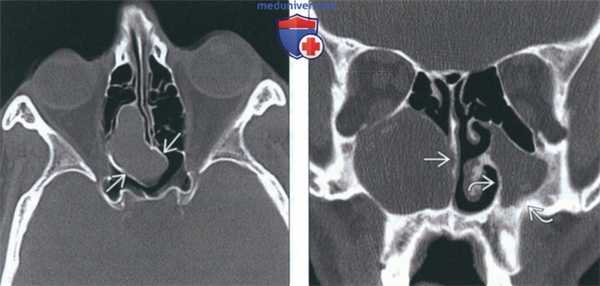

(Слева) При аксиальной «костной» КТ визуализируется заднее решетчатое мукоцеле, пролабирующее в основные пазухи, но не в орбиту. Определяется истончение и ремоделирование костей вокруг мукоцеле.

(Справа) При корональной «костной» КТ визуализируется крупное мукоцеле в правой верхнечелюстной пазухе (нетипичная локализация). Мукоцеле блокирует полость носа. Оцените изменения, обусловленные хроническим левосторонним гайморитом, - снижение объема пазухи и истончение стенок.

(Слева) На аксиальной КТ в костном окне определяется мукоцеле задних ячеек решетчатой пазухи, распространяющееся в сфеноидальные пазухи, но не в глазницу. Костная пластинка на периферии мукоцеле истончена и видоизменена.

(Справа) На корональной КТ в костном окне в правой верхнечелюстной пазухе (нетипичная локализация) определяется мукоцеле большого размера, приводящее к обструкции полоаи носа. Обратите внимание на признаки хронического левоаороннего гайморита: уменьшение объема пазухи и утолщение ее стенок.